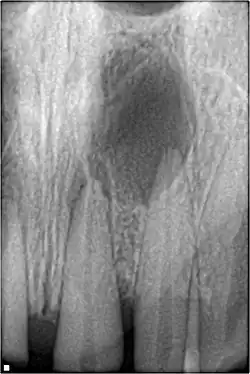

Periapical radiograph showing peri-radicular radiolucency and bone loss caused by an odontogenic infection under the roots of two anterior teeth in a 30-year-old patient

An odontogenic infection is an infection that originates within a tooth or in the closely surrounding tissues.[1] The term is derived from odonto- (Ancient Greek: ὀδούς, odoús – 'tooth') and -genic (Ancient Greek: -γενής, -γενῶς; -genḗs, -genôs – 'birth'). The most common causes for odontogenic infection to be established are dental caries, deep fillings, failed root canal treatments, periodontal disease, and pericoronitis.[2] Odontogenic infection starts as localised infection and may remain localised to the region where it started, or spread into adjacent or distant areas.

It is estimated that 90–95% of all orofacial infections originate from the teeth or their supporting structures and are the most common infections in the oral and maxilofacial region.[3] Odontogenic infections can be severe if not treated and are associated with mortality rate of 10 to 40%.[4] Furthermore, about 70% of odontogenic infections occur as periapical inflammation, i.e. acute periapical periodontitis or a periapical abscess.[3] The next most common form of odontogenic infection is the periodontal abscess.[3] Despite being more common in underprivileged regions, odontogenic infections affect people from all over the world, even in developed countries.[5]